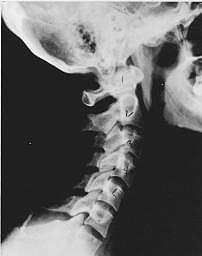

Subluxation Degeneration - Normal This is a side x-ray view of the neck. As with all the pictures you will see on this page, the patient is looking to the right of the screen, so you are viewing the right side of their neck. We will call this picture a "near normal" spine. Compare this spine with the ones you will see below on this page. Notice the normal forward curve of the neck. This curve helps absorb shock. Notice how each of the disc spaces between C2 (second bone in neck) and C7 are thick and even, this again is normal. Also notice how the front portions (right on the x-ray) of each of the vertebrae (called the 'body' of the vertebrae) are fairly square with clear and well defined borders. This type of arrangement is normal in the neck. Normal vertebrae in other parts of the spine also have similar characteristics to what we see here. When subluxations occur and are left uncorrected, ongoing relentless changes occur that result in damage to the structure and function of the spine along with nerve damage and the resulting problems caused from improper nerve supply.